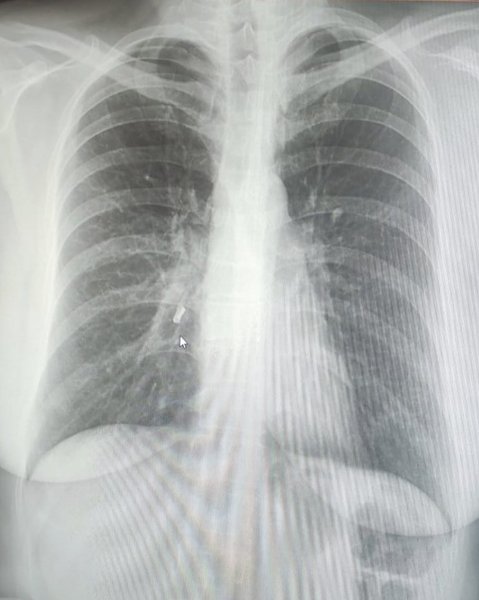

Выяснилось, что рентгенобследование ей не проводили, поскольку она кормила ребенка грудью. Женщине посоветовали обратиться за помощью к специалистам Центра легочного здоровья. Врач-пульмонолог осмотрела пациентку, а затем направила ее на рентгеноисследование. Результаты обследования и обнаружили у нее в правом нижне-щеточном бронхе часть зуба.

Медики выяснили, что часть зуба оказалась в легких во время родов, происходивших путем кесарева сечения. Во время экстренной процедуры он откололся.